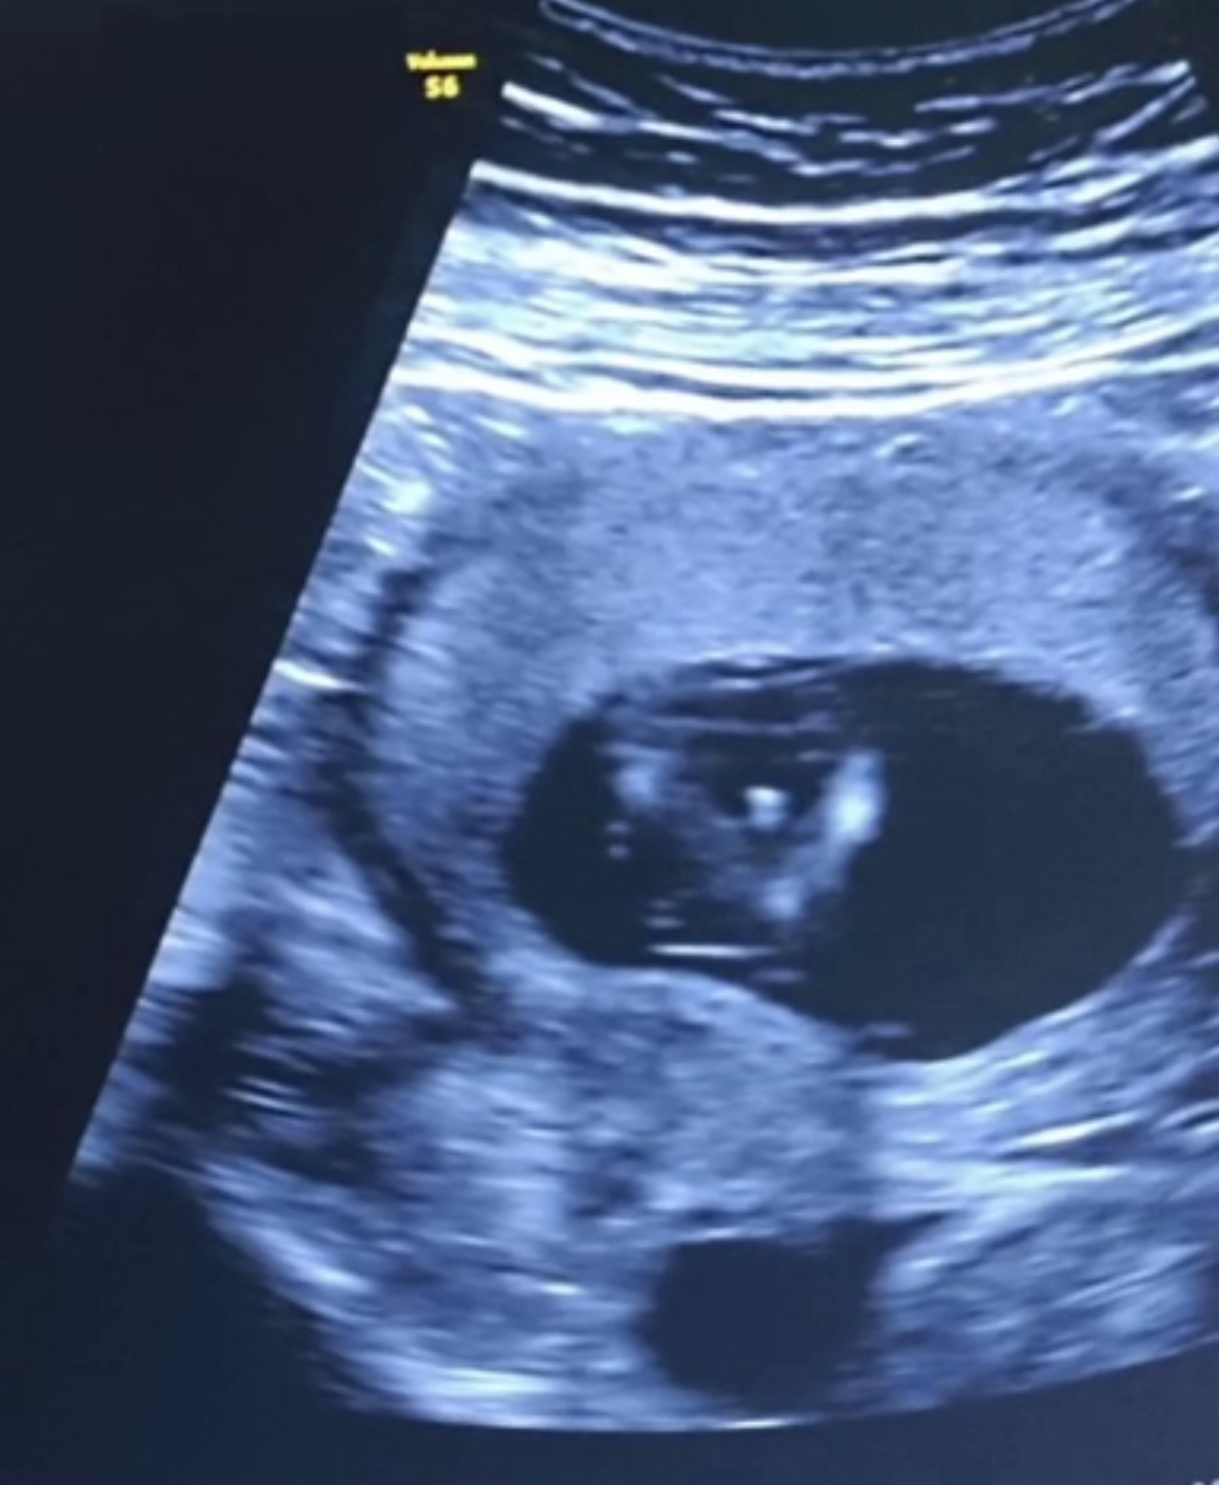

saba77o مدیر استارتر عضویت: 1398/06/21 تعداد پست: 598 عنوان جنسیت چیه 524 بازدید | 65 پست هفته ۱۳ هستم دکتر گفت صد در صد نمیتونم بگم جنسیت چیه امروز | 11:35 0 نفر لایک کرده اند ... گزارش تاپیک نامناسب

saba77o مدیر استارتر عضویت: 1398/06/21 تعداد پست: 598 حالا گذاشتی ما بهت بگیم جنسیتشو🙁 آخه خب دکتر میگه صد در صد نیست . میخواستم ببینم کسی این مدلی عکس داشته بگه جنسیت چی بوده

saba77o مدیر استارتر عضویت: 1398/06/21 تعداد پست: 598 این که صدرصدی پسره مطمعنی ؟ پس چرا دکتر میگه صد در صد نیست میشه بند ناف یا چیز دیگه باشه؟ من بارداری اولمه نمیدونم